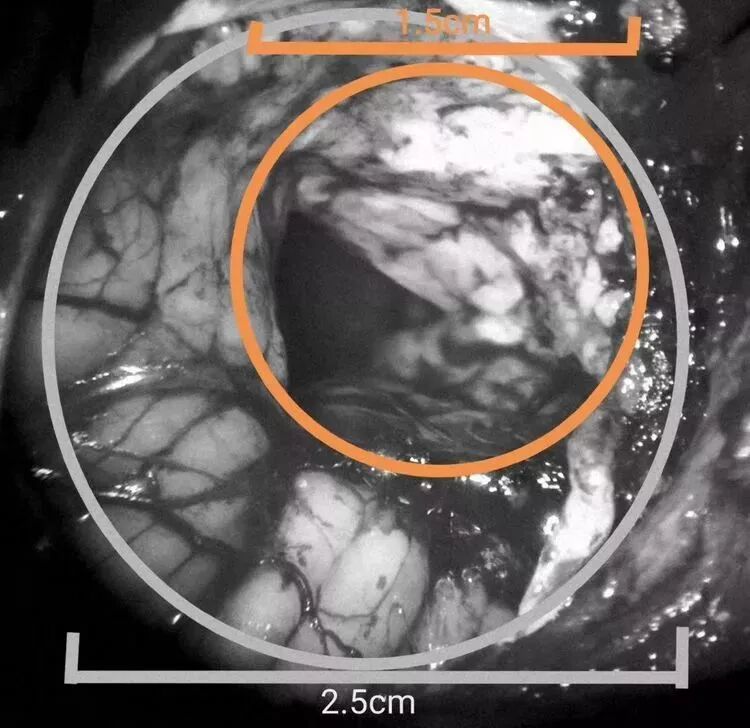

手术行左侧旁正中入路,应用锁孔通道技术,骨孔直径2.5cm,皮层通道1.5cm,先用内镜清除血肿,ICP下降,显微镜下清除IV脑室内积血,责任血管止血可靠,术毕。

骨孔直径2.5cm(图3白色圈为骨孔范围),皮层通道直径1.5cm(图3黄色圈为皮层通道直径)。